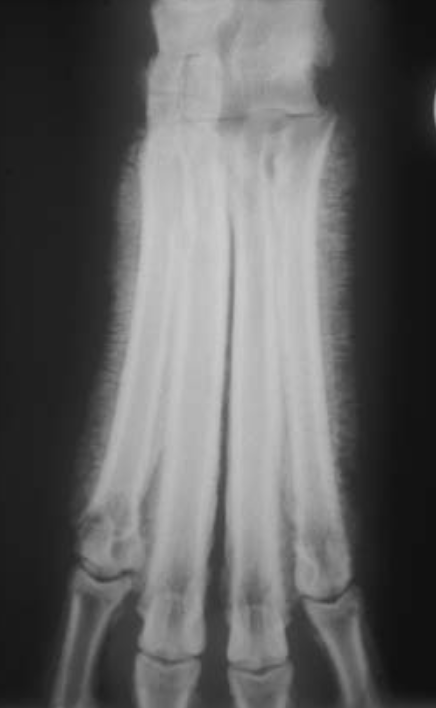

21

Q

A

Thick brush-like

periosteal reaction on the abaxial

surface of metacarpal V in a dog with hypertrophic osteopathy.